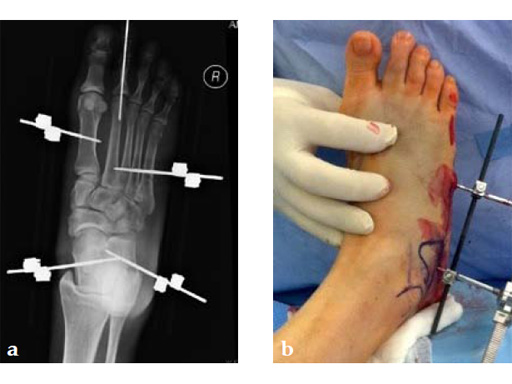

Case 6: VA -locking mesh plate

A 46-year-old female pedestrian was run over. Her foot was crushed by a car. It was a closed injury. She had no other bodily injuries and no medical problems. She sustained massive swelling and shear dorsal soft-tissue injury.

Case provided by Andrew Sands, New York, New York, USA